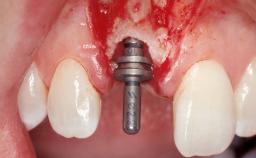

Placement Protocol Immediate implant placement

Loading Protocol Immediate

Retention Screw-retained Screw-retained

Provisional Implant-Supported Prosthesis Prosthodontic margin < 3 mm apical to mucosal margin Prosthodontic margin < 3 mm apical to mucosal margin